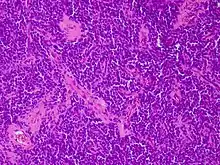

Micrograph of an H&E stained section of a peripheral PNET.

CD99 staining of tissue from peripheral PNET